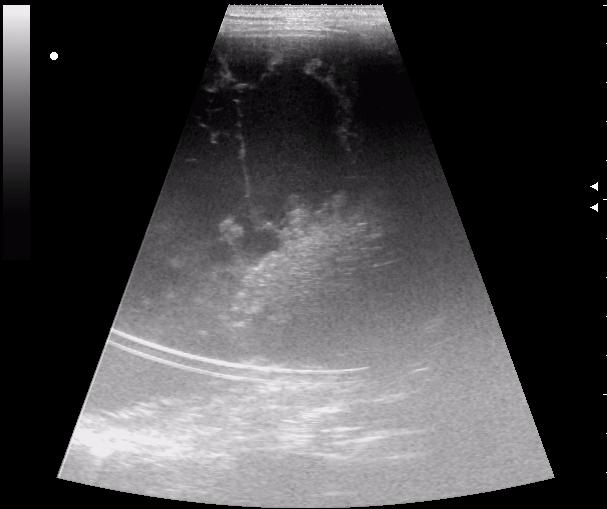

сегодня был селезёночный день.

>желтой стрелкой - это левый надпочечник?

Похоже.

Он обычно располагается больше кнутри от верхнего полюса почки и может досигать ее ворот.

Надежнее визуализировать ЛН из позиции, которую я показывал в известной Вам теме.